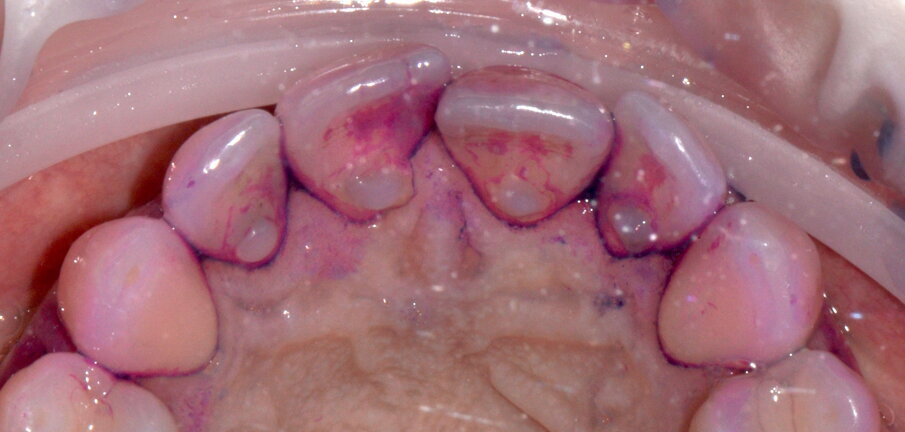

- Applicazione del rilevatore di placca bifasico: permette la distinzione fra i depositi di placca recenti da quelli meno recenti ( 1a-1c);

- Istruzione e motivazione all’igiene orale domiciliare guidati dal rilevatore di placca, mostrando visivamente al paziente l’attuale stato del suo mantenimento;

Figg. 1a-1c - Applicazione del rilevatore di placca che verrà usato come guida durante la terapia, nel versante vestibolare (1a), palatale (1b) e linguale (1c). Si noti lo scarso livello di igiene orale domiciliare e l’assenza di utilizzo dei presidi interdentali.